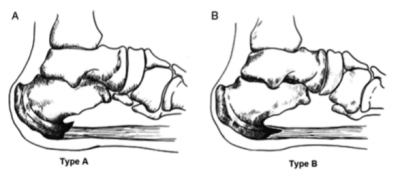

А почему формируется подошвенная шпора? Фасция все время тянет за свою точку крепления к кости, точнее она тянет надкостницу, покрывающую данную кость. При раздражении надкостница начинает стимулировать образование костной ткани, и мы получаем картину гребешка, или шпоры, на рентгенографии.

Иногда шпора выглядит как что-то издали напоминающее кость, иногда шпора перестраивается в истинную кость, но для понимания процесса это не критично. Иногда шпора бывает настолько массивной, что может даже произойти ее перелом.